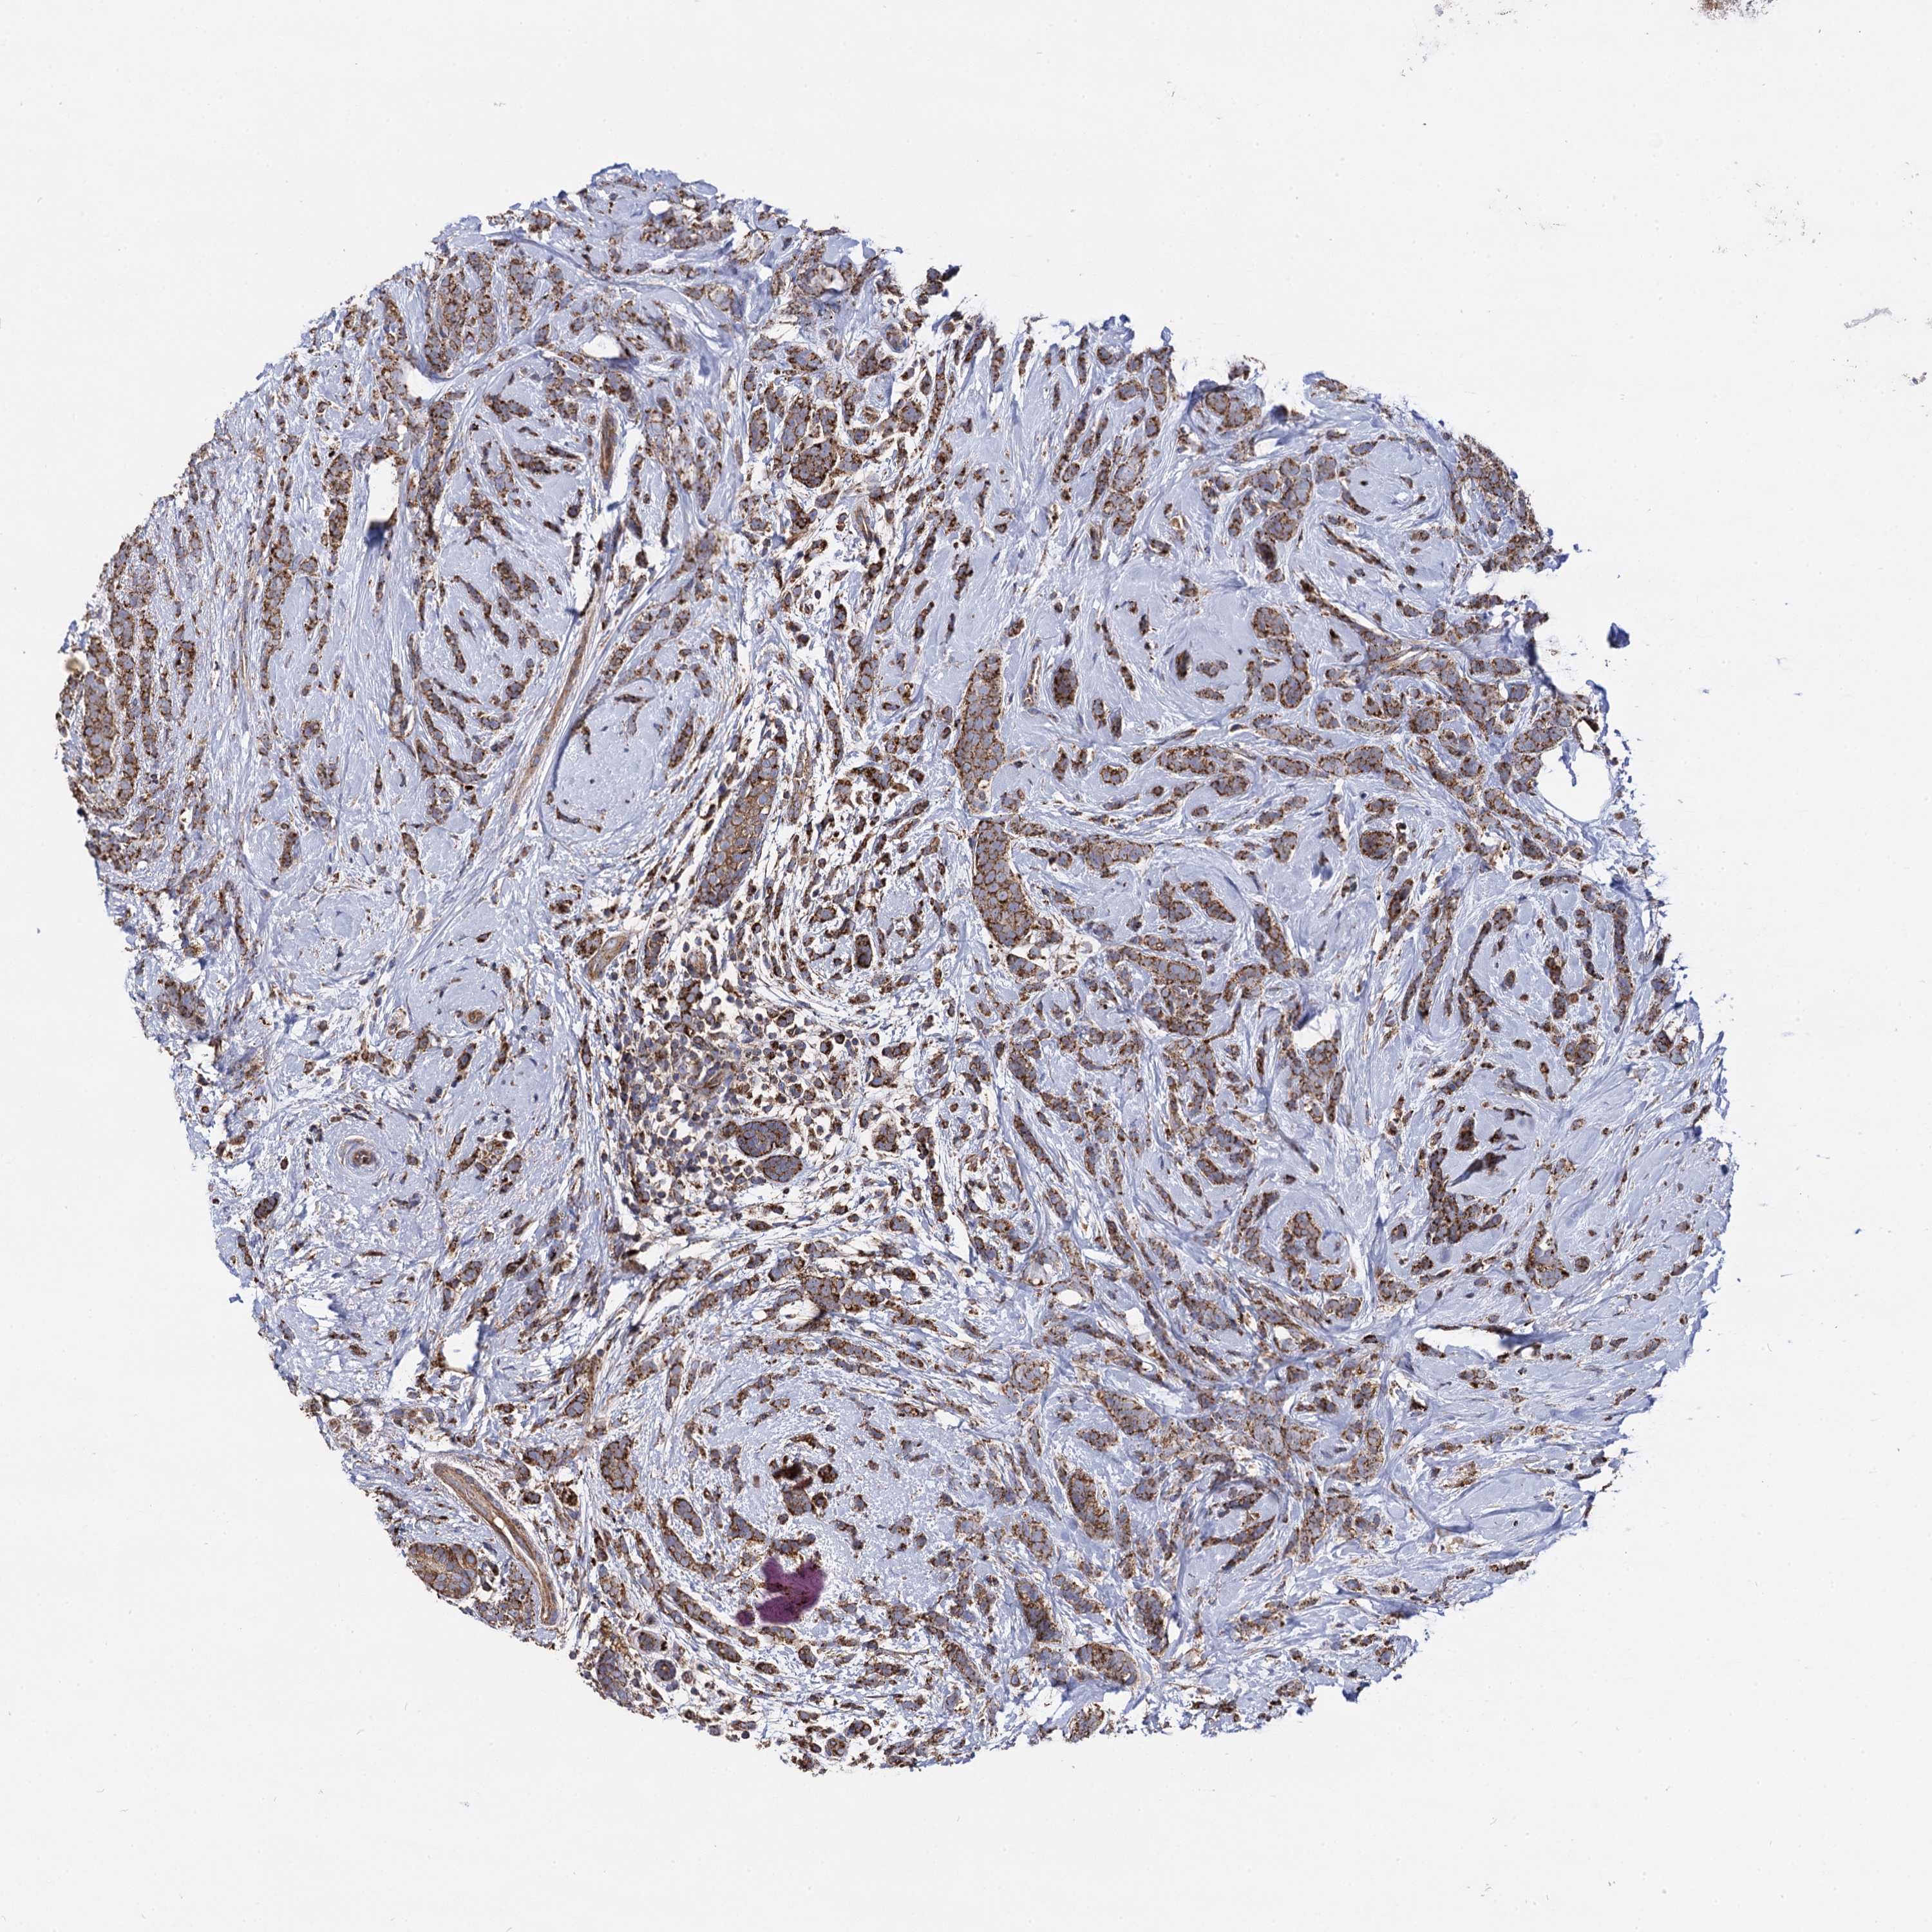

CANCER BREAST CANCER Show tissue menu

BRCA TCGA BRCA VALIDATION PROTEIN EXPRESSION